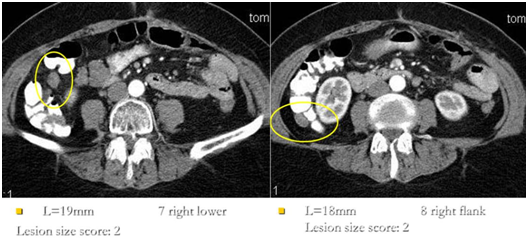

Figure 4 CT image of implants of right lateral canal and right iliac region.

Figure 5 Implants of abdominal surface of the right diaphragm on CT scan and intraoperative image.